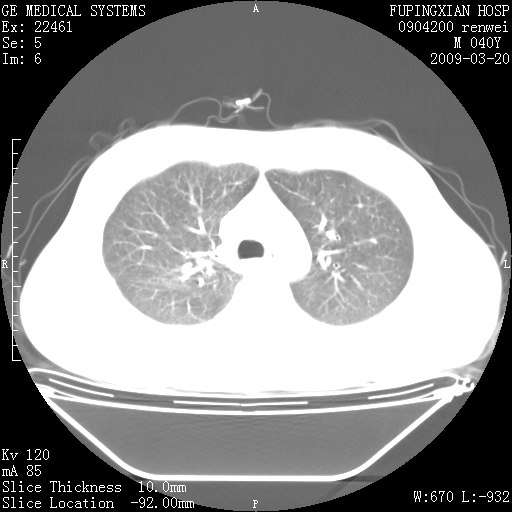

标题: CT18920:平时体健,体检时发现以下问题。 [打印本页]

标题: CT18920:平时体健,体检时发现以下问题。

单侧肺气肿表现,原因?   特发性或先天性可能

右肺气肿。

右肺局限性肺气肿

右肺局限性肺气肿。

右肺局限性肺气肿,有无呛咳史?

右肺局限性肺正常

双肺弥漫磨玻样改变,肺纹理增重,考虑早期间质纤维化伴局部阻塞肺气肿,[考虑黏液栓]

右肺局限性肺气肿;[考虑黏液栓]所致。

双肺弥漫磨玻样改变,右肺局限性肺气肿。病人没有症状?

考虑间质性肺炎伴右侧局限性肺气肿,

右肺局限性肺气肿;[考虑黏液栓]所致

先天性支气管闭锁

右肺局限性肺气肿,原因?先天支气管闭锁?粘液栓?